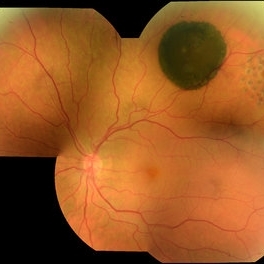

CHRPE CHRPEOct 8 2019 by DIEGO TOLENTINO CHRPE plus laser barricade around retinal break Photographer: Diego Tolentino Condition/keywords: congenital hypertrophy of the retinal pigment epithelium (CHRPE)